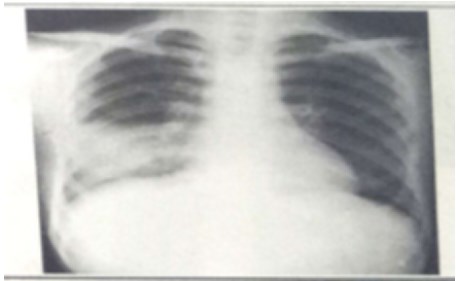

试题:男性,26岁,受凉后寒颤高热,咳嗽,咳铁锈色痰5天(2分

A.肺癌

B.气胸

C.正常胸片

D.肺炎

答案:D